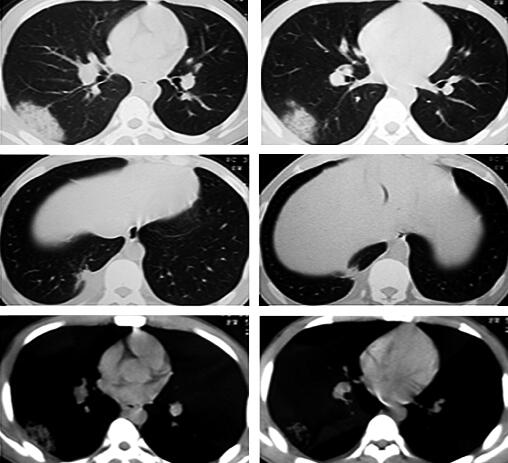

3.胸部CT:

右肺下叶外后基底段散在斑片及片状渗出影,部分病灶呈楔形,尖端指向肺门,右下叶后基底段近脊柱旁片状阴影内见密度减低区,病灶与胸膜粘连(图1)。

图1

评价:一个年青体壮、无肺部基础疾病的患者,胸部CT提示右肺下叶散在斑片影就会导致气短?患者无喘息,双肺无干湿啰音,无小气道疾病依据,影像学改变与临床症状之间的“不匹配”没有引起医生的高度重视;对于胸痛伴活动后气短的患者未行血气分析和D-dimer化验等进行常规鉴别诊断分析,导致临床思路偏离了正确方向。